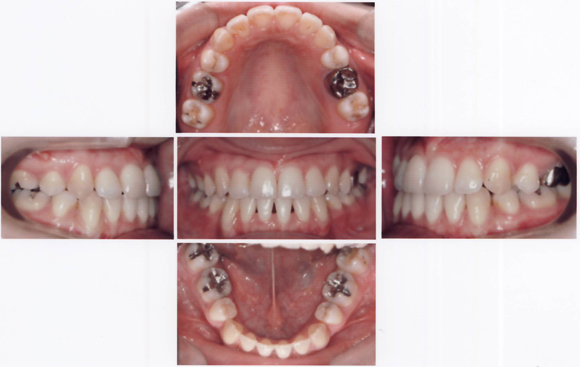

CASE1 下顎が出ているケース

術前

術後